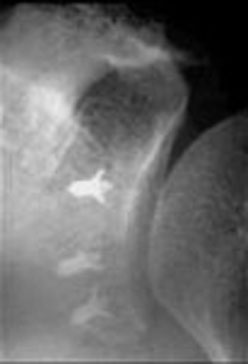

Ακτινογραφία που δείχνει τις άγκυρες μετά από

την αποκατάσταση μιας βλάβης Bankart